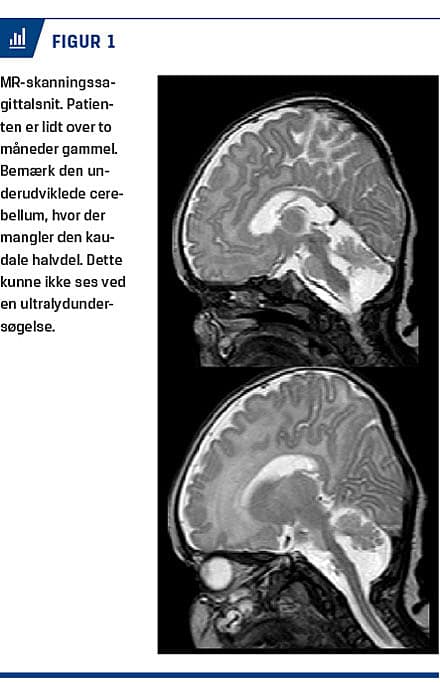

Målingerne af syre-base-forhold, kreatinkinaseniveau, thyroideaprofil samt infektions- og levertal var alle normale. En urinmetabolisk screening og øjenundersøgelse var også uden bemærkninger. Der blev tidligt lavet ultralydskanning af cerebrum, og skanningen viste ikke noget abnormt. En MR-skanning af cerebrum nogle uger senere viste en underudviklet cerebellum (Figur 1).